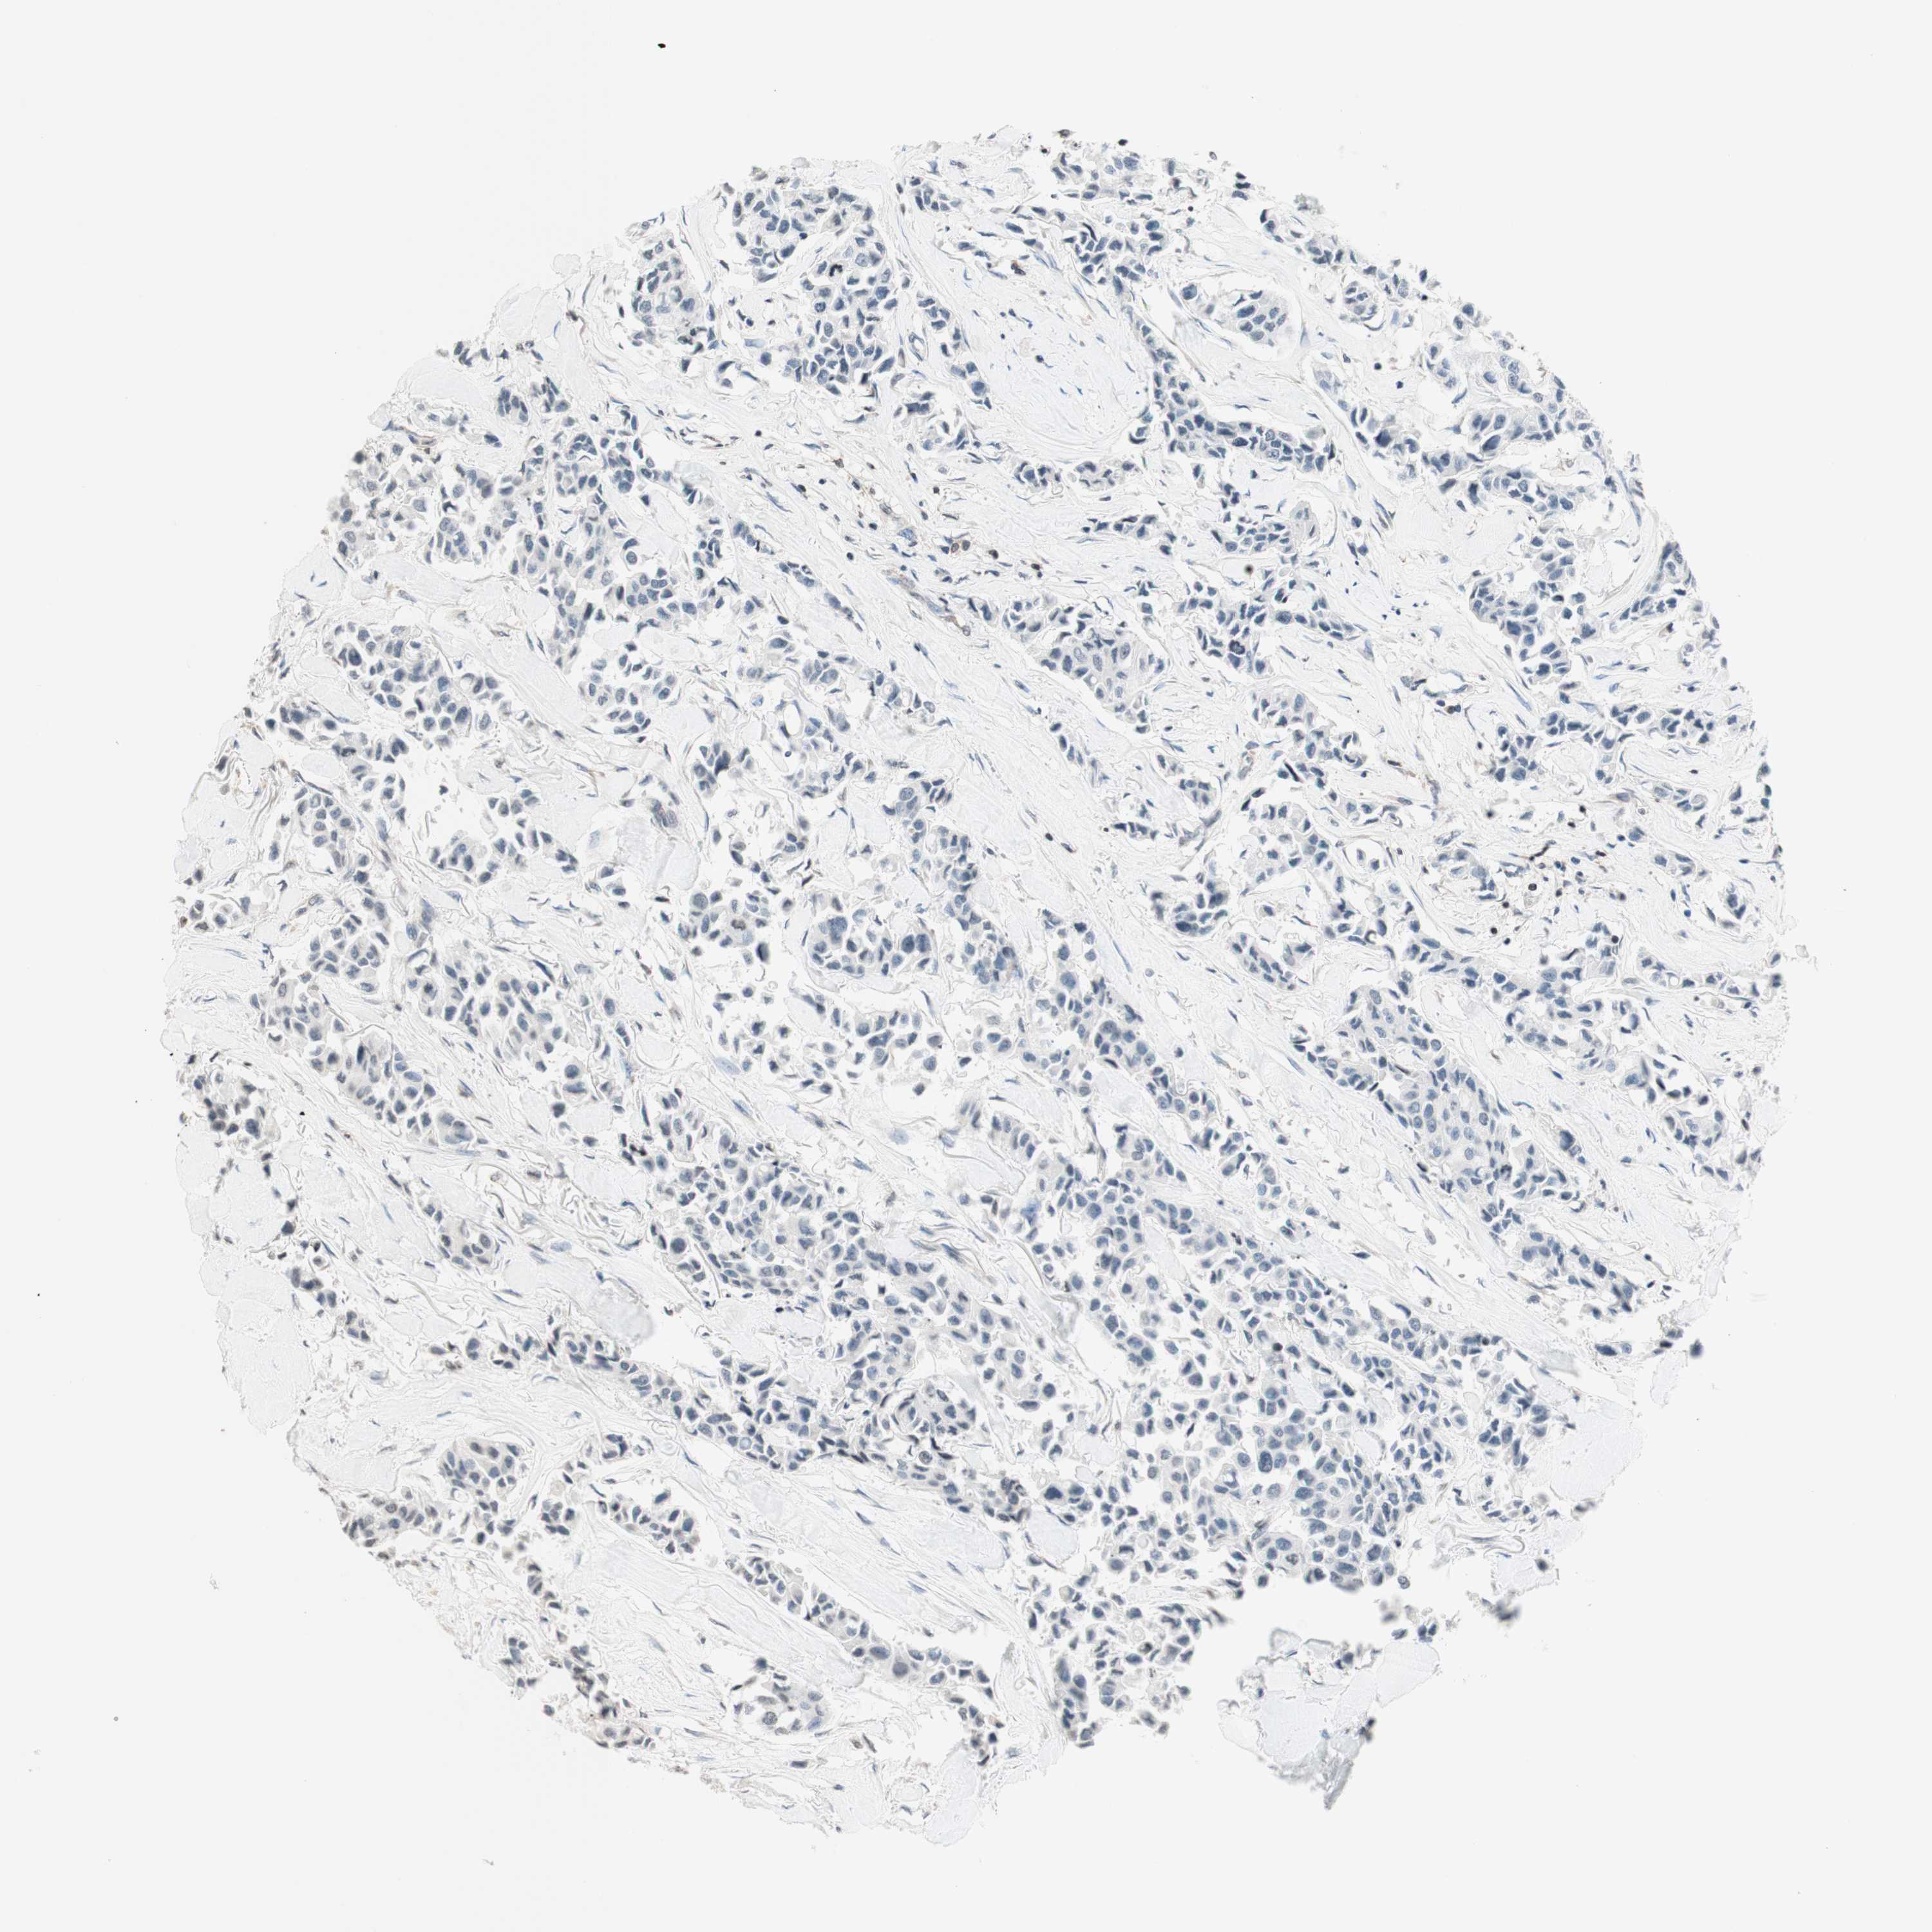

BRCA TCGA BRCA VALIDATION PROTEIN EXPRESSION

ANTIBODIES

AND

VALIDATION